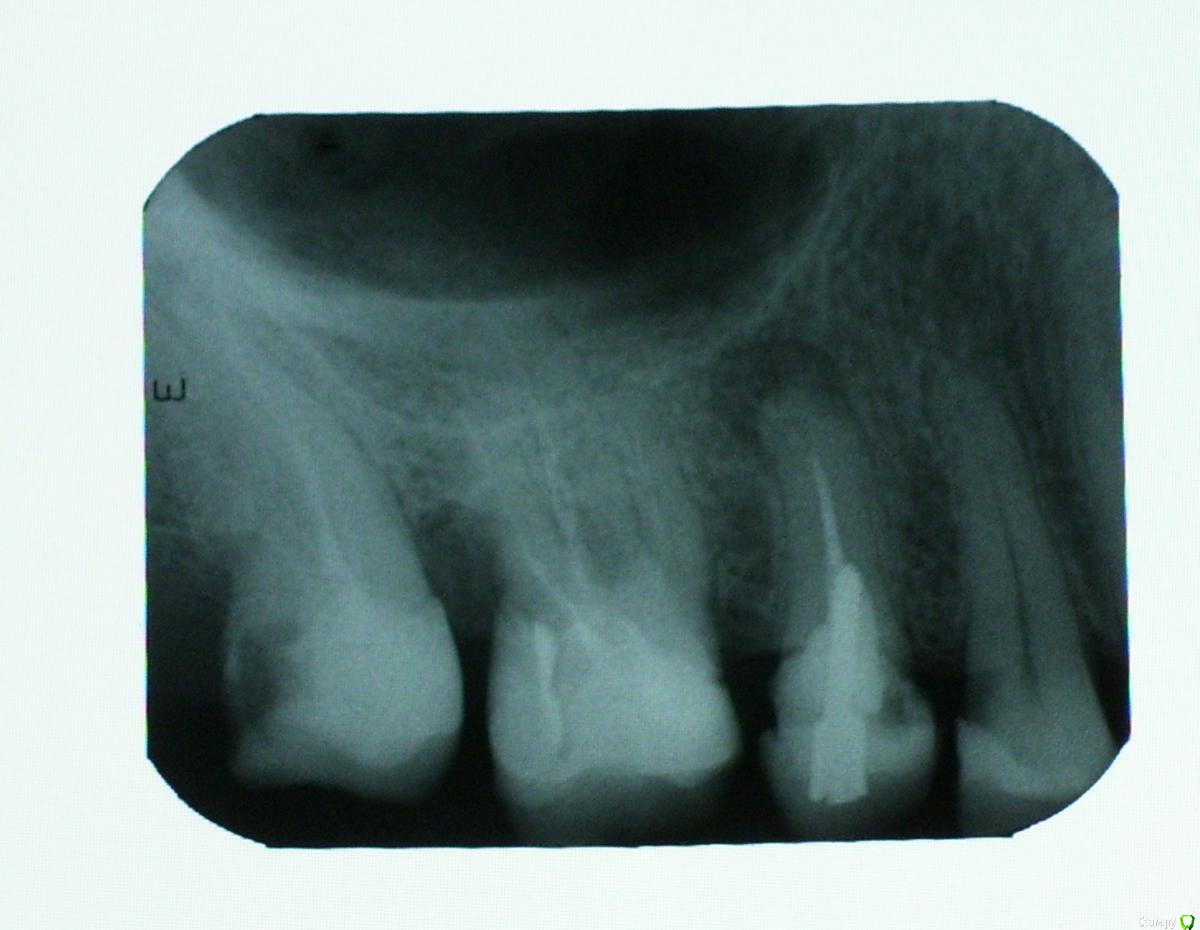

shishok Опубликовано 3 мая, 2016 Поделиться Опубликовано 3 мая, 2016 На верхушке 5го есть воспаление,каналы надо перелечивать . 1 Ссылка на комментарий

АнтонТЛТ Опубликовано 5 мая, 2016 Поделиться Опубликовано 5 мая, 2016 По снимку очень похоже 1 Ссылка на комментарий

red_butler Опубликовано 5 мая, 2016 Поделиться Опубликовано 5 мая, 2016 То есть Вы имеете в виду, что у меня неправильно сделаны пломбы на 6 и 7 зубах?проблема в лечении корневых каналов, и в том что на 5, 6, 7 стоят пломбы а должны быть коронки 2 Ссылка на комментарий

red_butler Опубликовано 5 мая, 2016 Поделиться Опубликовано 5 мая, 2016 Скажите пожалуйста, перелечивать нужно только каналы 5-ки, или в 6-ке и 7-ке они тоже плохо залечены?Все три перелечивать 2 Ссылка на комментарий

IvanK Опубликовано 5 мая, 2016 Поделиться Опубликовано 5 мая, 2016 Все три перелечиватьи протезировать 2 Ссылка на комментарий

red_butler Опубликовано 10 мая, 2016 Поделиться Опубликовано 10 мая, 2016 в четверке тоже периодонтит.ищите врача. 2 Ссылка на комментарий